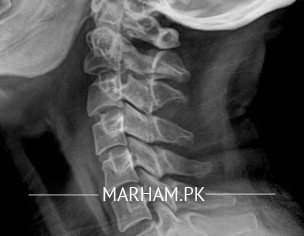

3 month sy dizziness ot forhead or head py crwaling and numbnes ho ryi hai doctotor ny ct scan karwyaa jo k mention kiya hai or cervical cray and sinnses k xray karwyee hain kindly btayin kiya msla hai all reports are mention

Neck muscular spasm Rest is normal

Bilateral small cervical ribs on x-ray

Normal CT brain

bilateral cervical ribs ... extra ribs hoti hae..lekan enka koi nuqsan nahi hota , Jo ke x Ray pe nazar again hae .

aor CT scan normal hae .